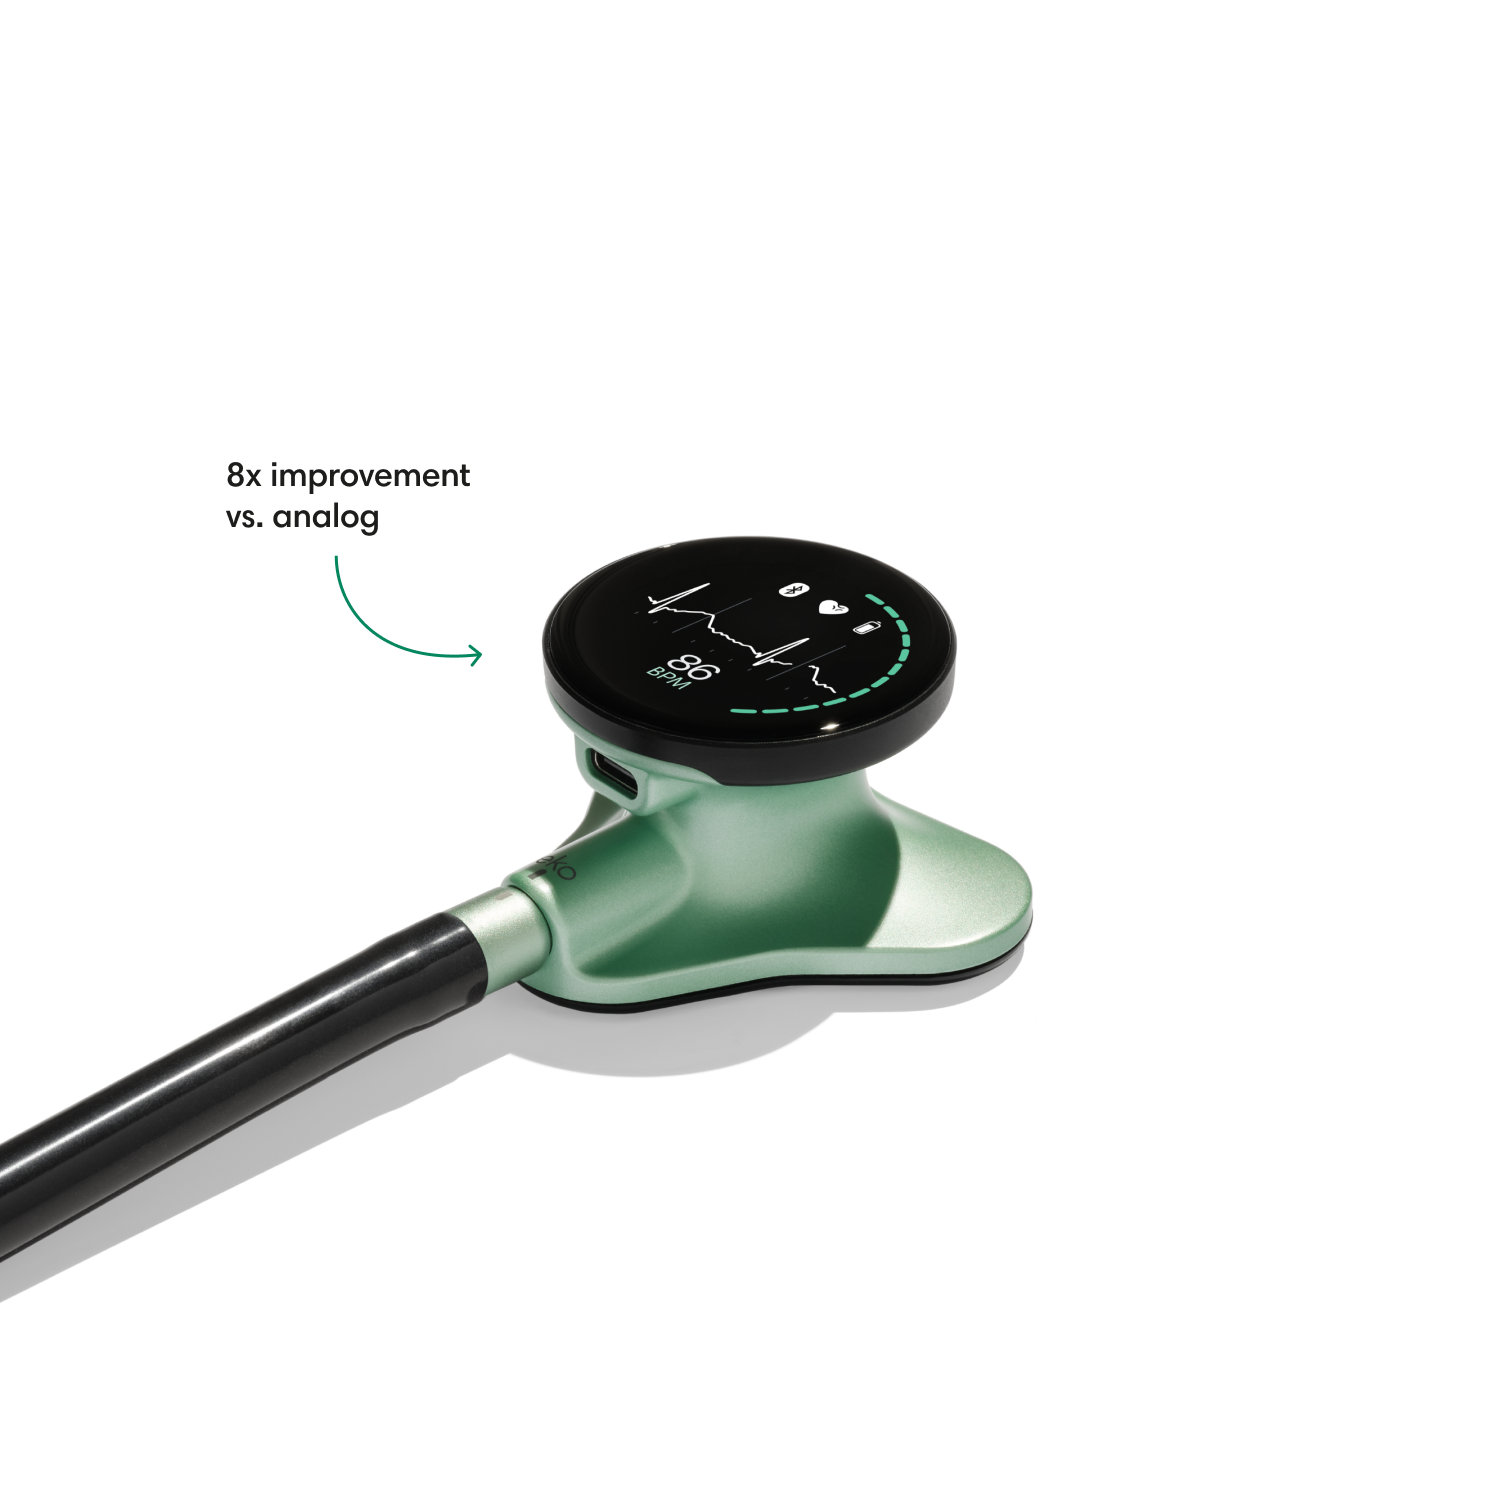

Instead of using a hollow tube like with an analog stethoscope, heart and lung sounds are delivered digitally through ear tip speakers. This results in unparalleled audio quality and sound cancellation.

- Reduces background noise 8x better vs. a typical analog stethoscope.